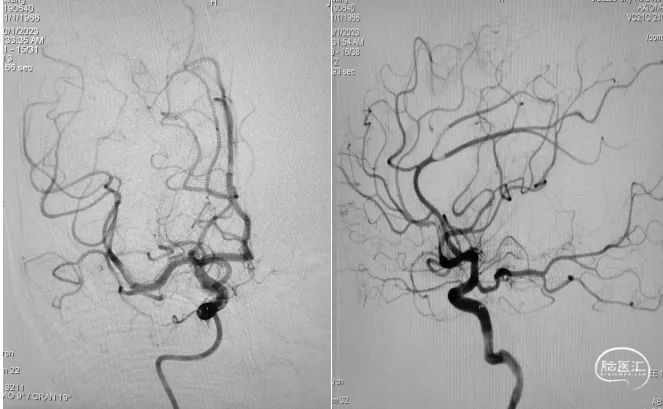

造影提示右侧大脑中动脉血流通畅。

取栓装置中可见白色胶冻状血栓。

6F心玮吞川®颅内血栓抽吸导管行基底动脉血栓抽吸。

复查造影示基底动脉及其分支显影良好,取栓装置中可见白色胶冻状血栓。